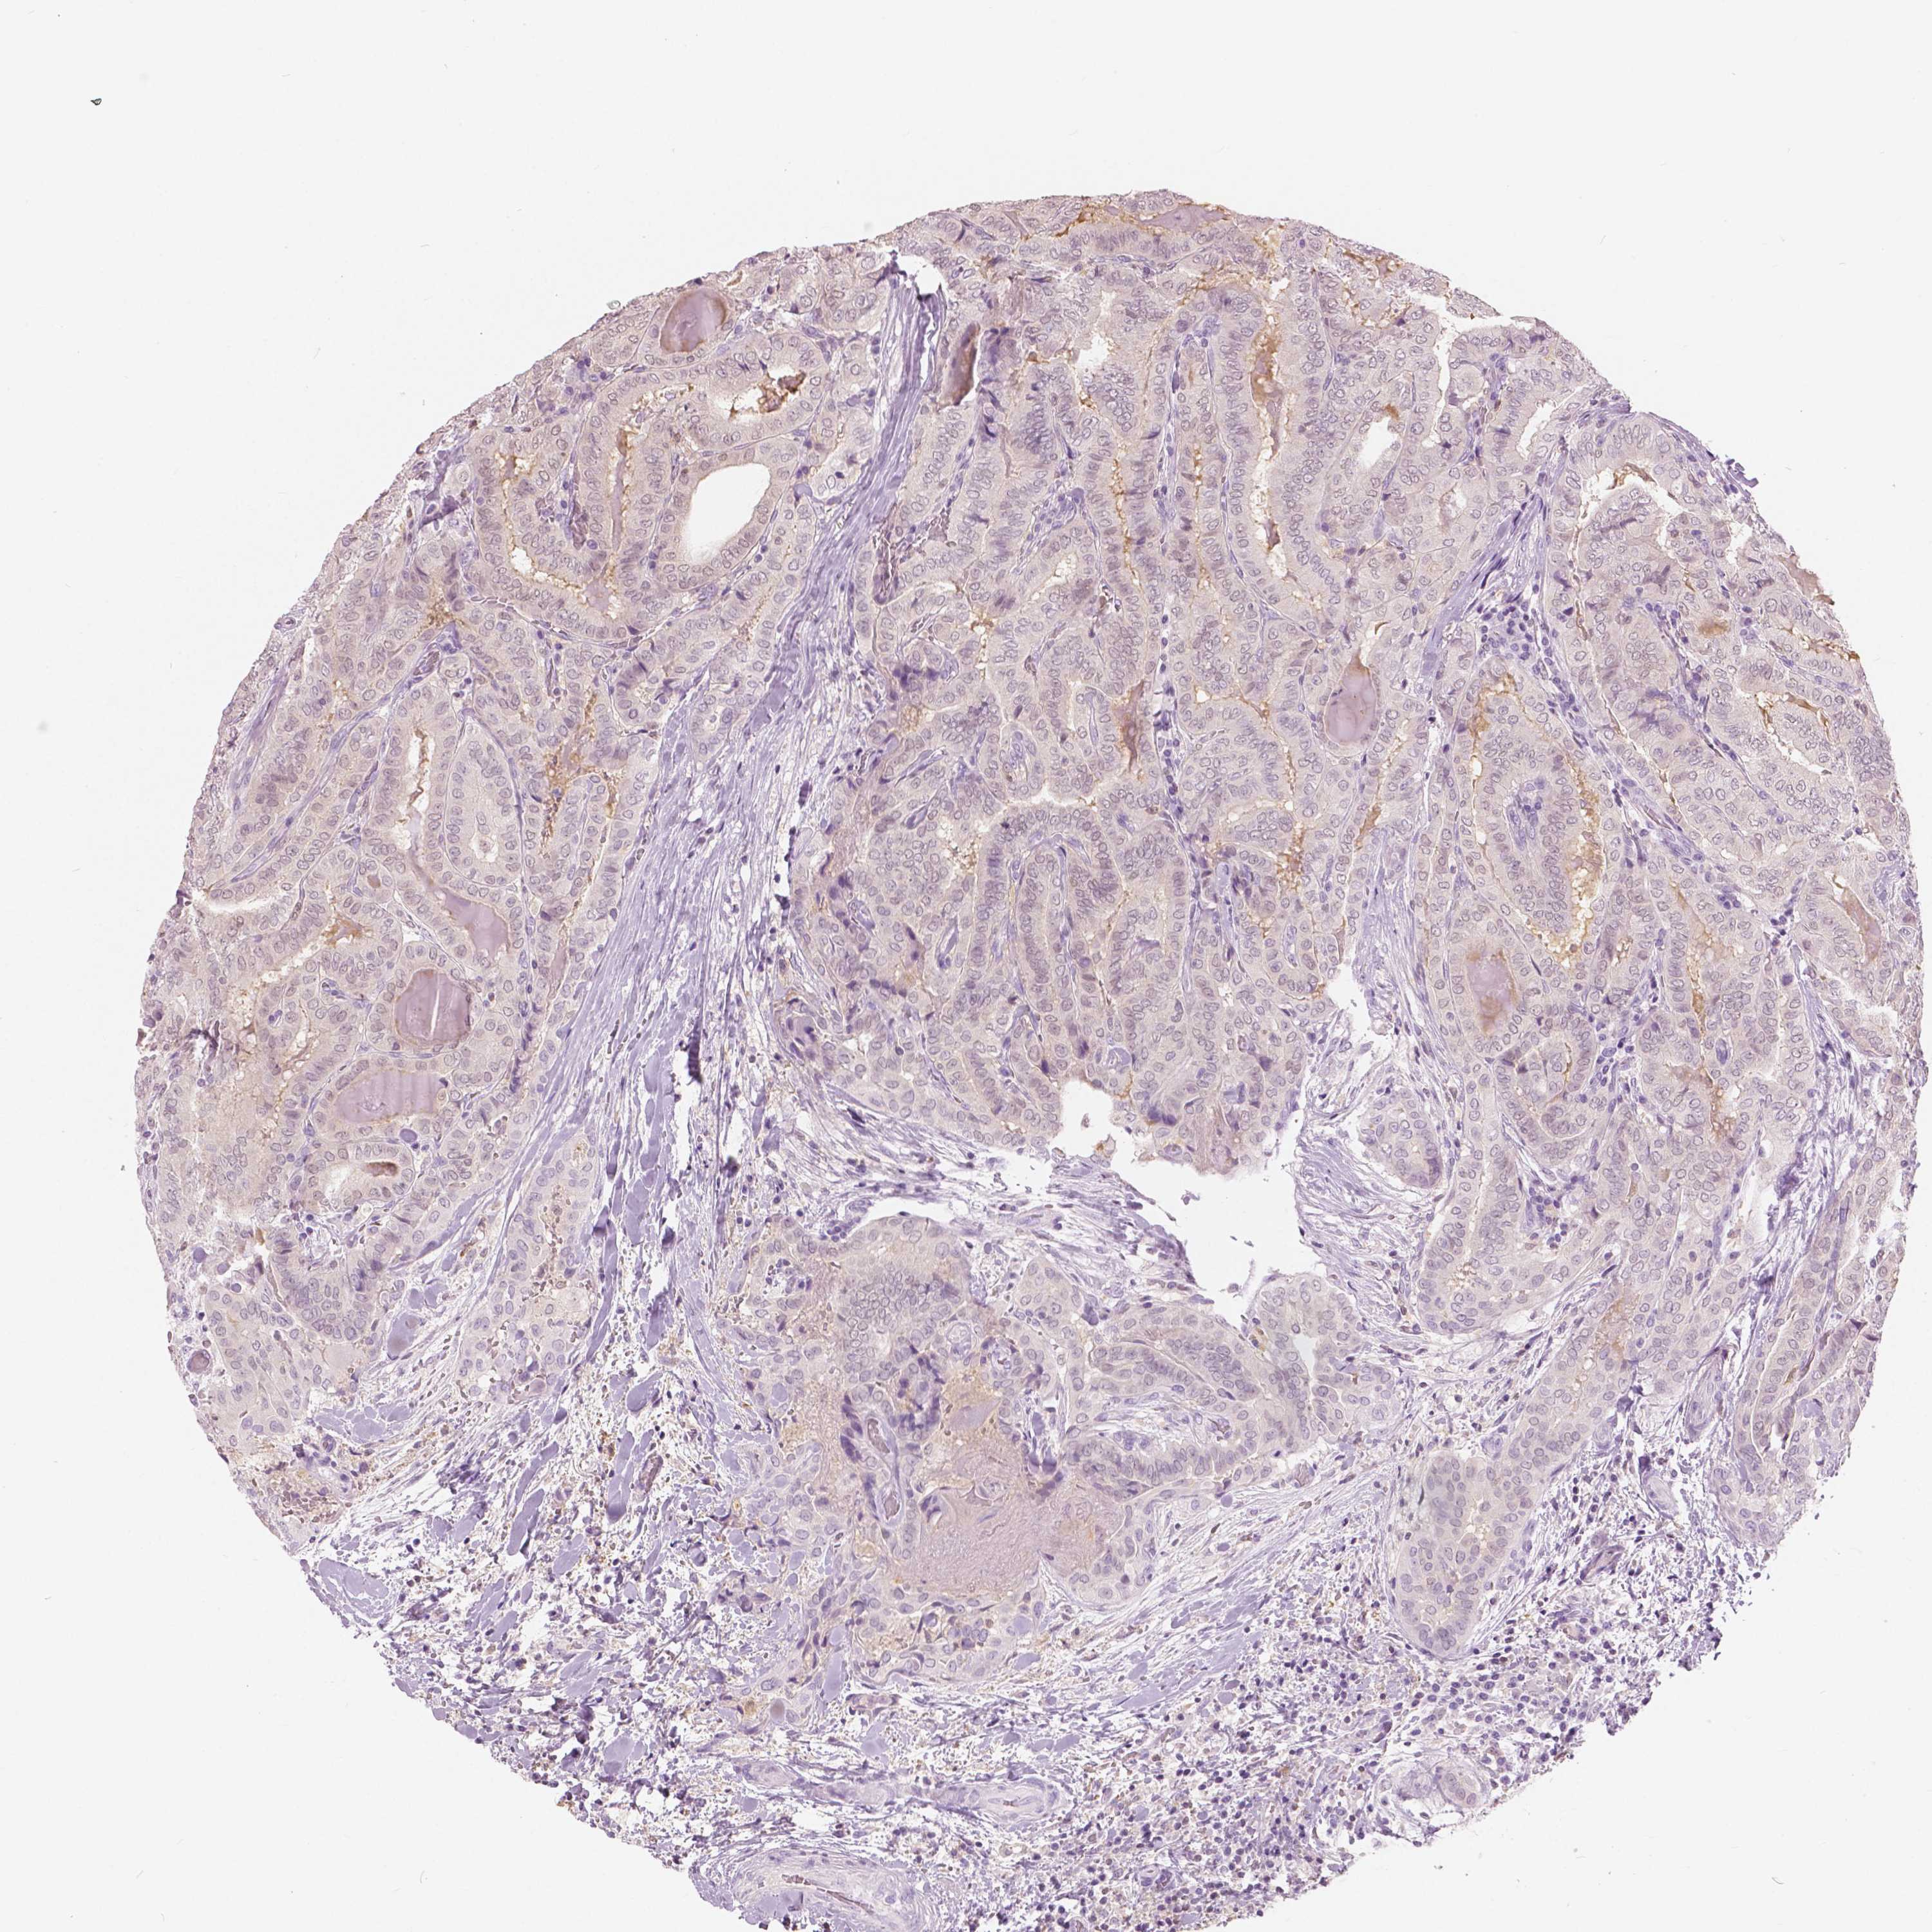

THYROID CANCER - Protein expressioni

A mouse-over function shows sample information and annotation data. Click on an image to view it in a full screen mode. Samples can be filtered based on level of antibody staining by selecting one or several of the following categories: high, medium, low and not detected. The assay and annotation is described here.

Note that samples used for immunohistochemistry by the Human Protein Atlas do not correspond to samples in the TCGA dataset.

Antibody stainingi

Antibody staining in the annotated cell types in the current human tissue is reported as not detected, low, medium, or high, based on conventional immunohistochemistry profiling in selected tissues. This score is based on the combination of the staining intensity and fraction of stained cells.

Each image is clickable and will lead to virtual microscopy that enables deeper exploration of all samples and also displays staining intensity scores, fraction scores and subcellular localization as well as patient and tissue information for each sample.

Antibody HPA035472

Antibody HPA035473

Antibody HPA064835

Staining

High

Medium

Low

Not detected

Intensity

Strong

Moderate

Weak

Negative

Quantity

>75%

75%-25%

<25%

None

Location

Nuclear

Cytoplasmic/membranous

Cytoplasmic/membranous,nuclear

Papillary adenocarcinoma, NOS

Follicular adenoma carcinoma, NOS